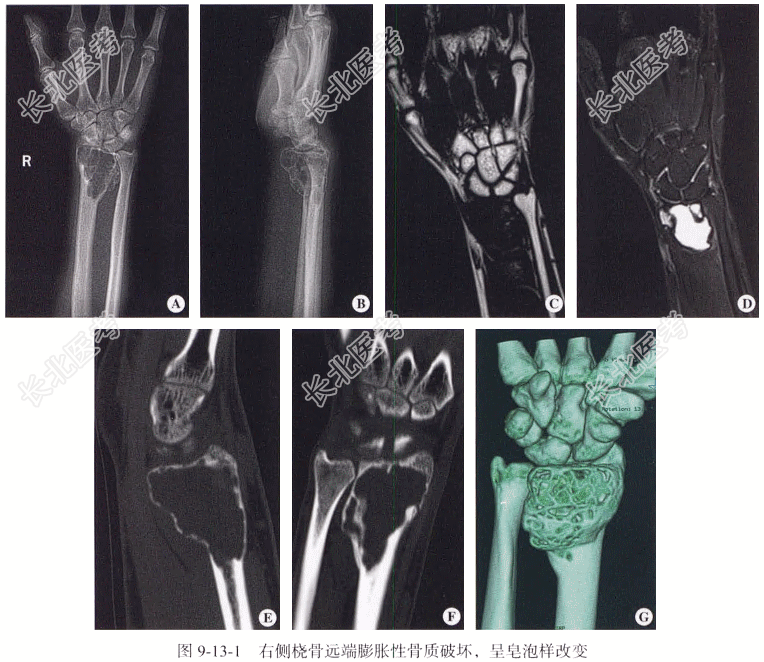

【影像所见】DR平片上右侧桡骨远端偏心性横向生长、轻度膨胀性骨质破坏,其内可见纤细骨嵴,构成分房状、皂泡样改变,骨壳变薄,其轮廓完整。

CT平扫:CT矢状位、冠状位及三维重建显示右侧桡骨远端偏心性、多房型、膨胀性骨质破坏,其内可见纤细骨嵴,构成分房状、皂泡样改变,骨壳变薄,其轮廓完整。

MRI:T₁WI冠状位平扫显示病变呈均匀的低信号,其内可见多发等信号分隔影,病灶边缘界线清晰;在T₂WI脂肪抑制上表现为明显的高信号,其内可见多发等信号分隔影,边界清晰。

【影像图片】见图9-13-1。